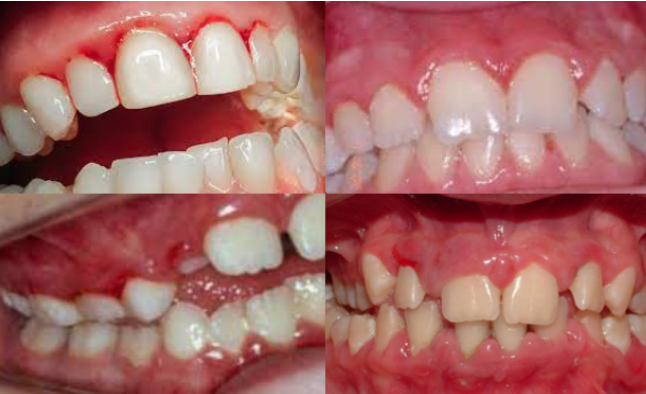

A periodontite agressiva juvenil é uma doença gengival séria que afeta jovens. Ela causa destruição rápida do osso e dos tecidos que sustentam os dentes. O diagnóstico precoce é crucial para evitar a perda dentária.

A periodontite agressiva juvenil, quando não tratada, pode trazer sérias consequências para a saúde bucal. Por isso, a limpeza profissional não é só um cuidado estético, é a base para o controle dessa condição. Dentistas e higienistas têm as ferramentas e o conhecimento para remover aquela placa bacteriana e o tártaro que o dia a dia em casa não alcança. É um passo fundamental para frear a progressão da doença.

Nesse tratamento, o foco é a remoção minuciosa das bactérias. Os profissionais utilizam instrumentos específicos para limpar profundamente as bolsas periodontais, que são aquelas espaços que se formam entre o dente e a gengiva quando a doença avança. O objetivo é criar um ambiente bucal mais saudável, onde a gengiva possa começar a se recuperar e a inflamação diminua. É um trabalho delicado, que exige precisão.

Gengivas que sangram facilmente, inchaço e vermelhidão são os primeiros alertas. Mau hálito persistente também pode indicar algo. Observe o sorriso do seu filho atentamente.